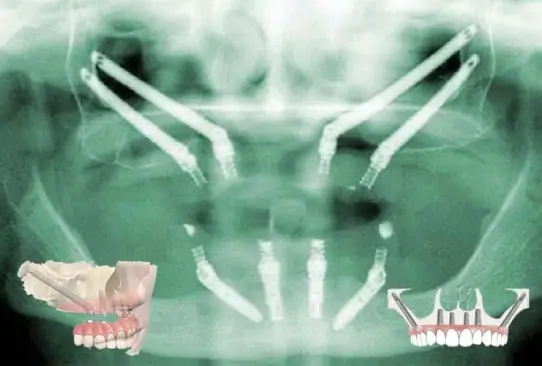

مراحل ایمپلنت کامل فک بالا و فک پایین تفاوتهایی با هم دارد و باید به صورت کاملا تخصصی کاشت ایمپلنت ها انجام شود. ایمپلنت کامل فک بالا معمولا به روش all-on-4 برای افرادی انجام میشود که همه دندانهایی خود را از دست دادهاند. اما برای سایر افراد از روشهای متداول کاشت ایمپلنت استفاده میشود.

در این روش 4 ایمپلنت در فک بالا قرار گرفته و پل ثابت روی آنها نصب میشود. دو ایمپلنت در جلوی فک بوده و دو ایمپلنت در پشت با زاویه 45 درجه قرار میگیرند. در این روش به دلیل زاویهدار بودن ایمپلنتها نیازی به جراحی پیوند استخوان نیست و بیمار در مدت کوتاه تری میتواند کاشت ایمپلنت برای دندانهای خود انجام دهد. این روش به دلیل مقاومت بالا و ظاهر طبیعی طرفداران زیادی داشته جز گزینههای محبوب نزد دندانپزشکان و بیماران است. مراحل ایمپلنت فک بالا در این روش کوتاه است و نسبت به پروتز دندان مصنوعی انتخاب بهتری محسوب میشود. از این روش میتوان برای فک پایین هم استفاده کرد و جایگزینی کامل دندان های فک بالا و پایین را با این تکنیک انجام داد.